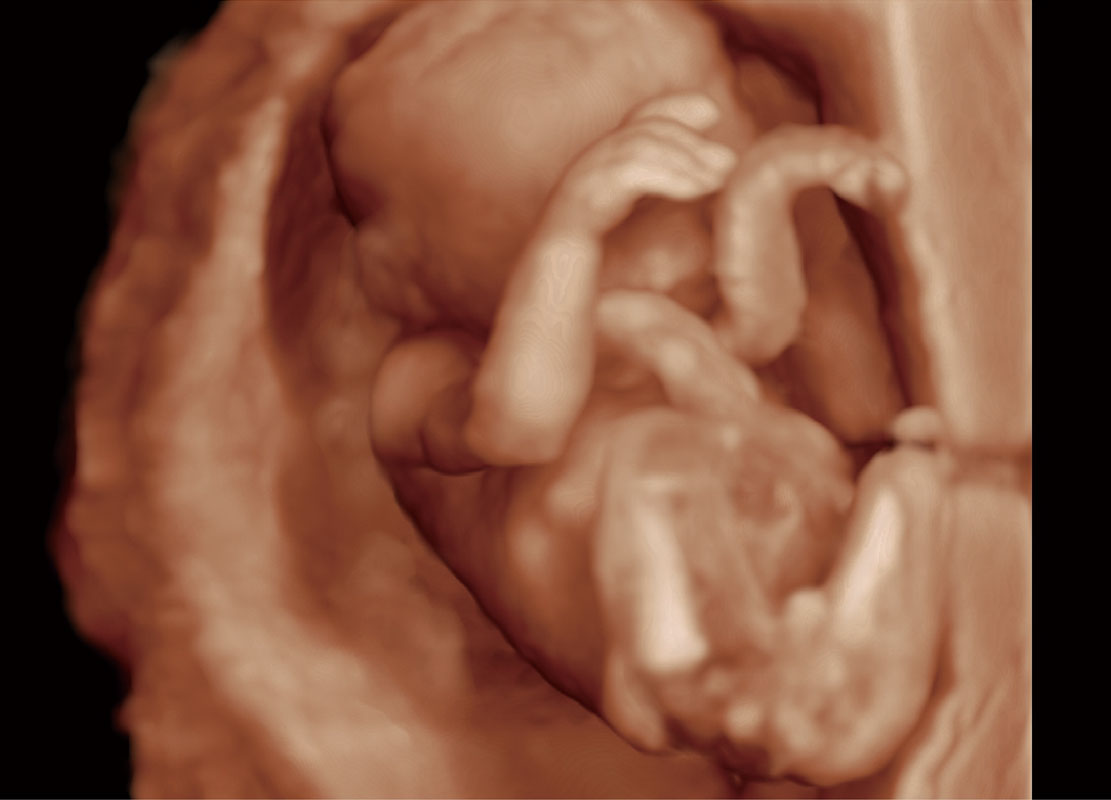

P60搭载一系列胎儿心脏成像技术,实现精细的胎儿心脏评估。

四腔切面

四腔心血流

右室双出口

胎心容积成像